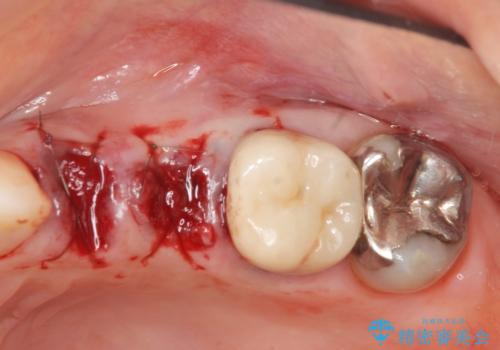

歯の穿孔(内部穴が開いている状態)破折等、歯を保存することができない問題が小臼歯には認められたので抜去を行います。

抜去後の補綴治療は長いブリッジではなくインプラント治療を希望されましたが、穿孔・破折による周囲の骨吸収をリカバリーすべく骨の造成を伴うインプラント治療を計画します。

今回はが原因で失われてしまった骨の幅を回復することで長期的な予後を見込めるインプラント治療を行うことができました。